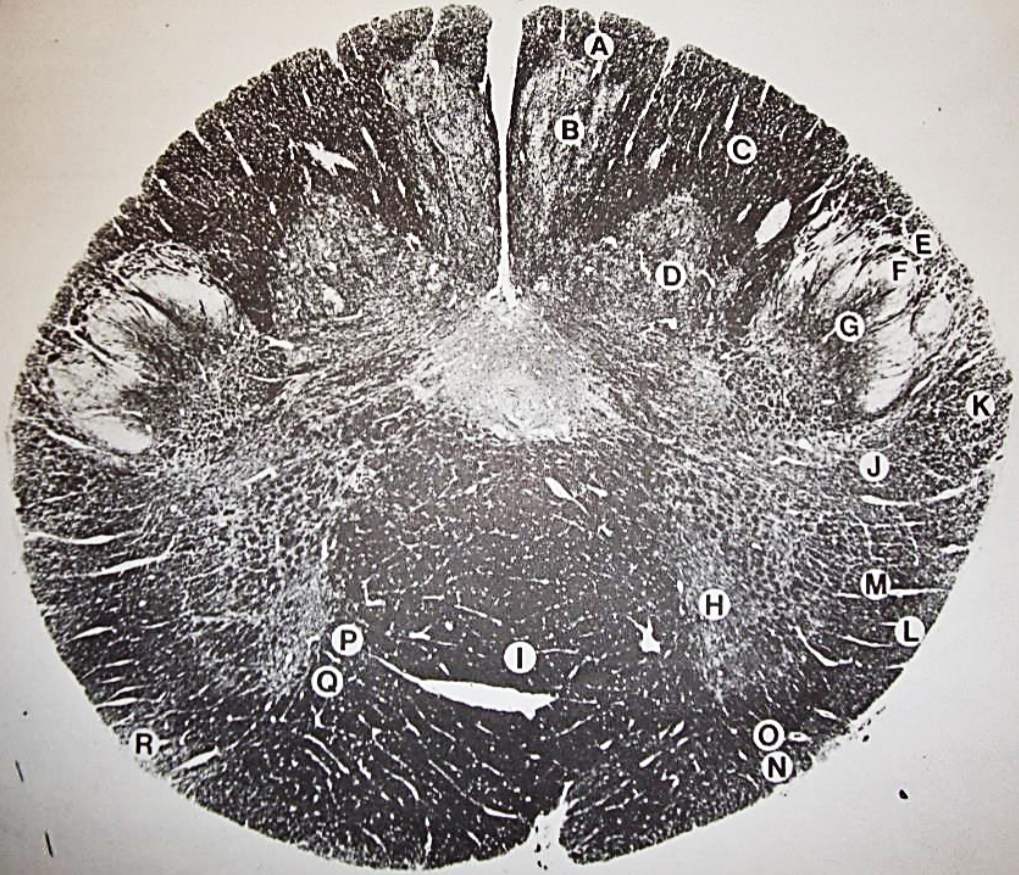

A

fasciculus gracilis

B

gracile nucleus

C

fasciculus cuneatus

D

cuneate nucleus

F

internal arcuate fibers

G

decussation of internal arcuate fibers

H

medial lemniscus

I

hypoglossal nucleus

J

dorsal motor nucleus vagus

K

solitary fasciculus

L

solitary nucleus

M

dorsal longitudinal fasciculus

N

spinal trigeminal tract

O

spinal trigeminal nucleus

P

posterior spinocerebellar tract

Q

anterior spinocerebellar tract

R

spinal lemniscus

S

lateral vestibulospinal tract

T

rubrospinal tract

U

lateral reticular nucleus

V

medial accessary olivary nucleus

W

pyramidal (corticospinal) tract

X

arcuate nucelus

Y

medial longitudinal fasciculus

Z

tectospinal tract

a

fascicles of hypoglossal nerve